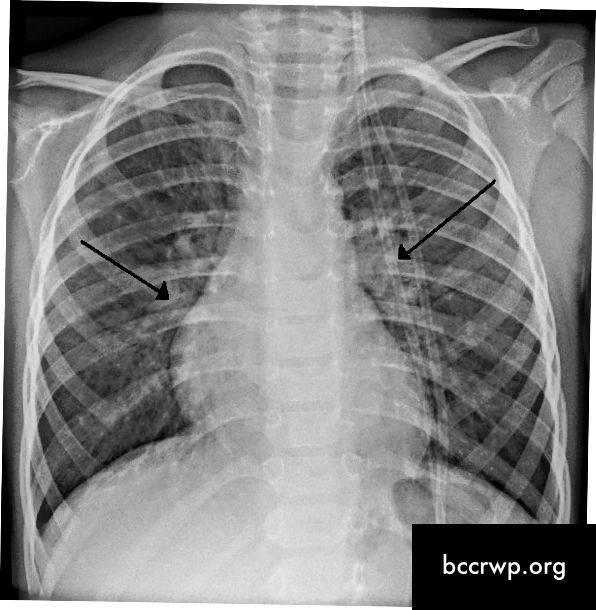

Get the latest news and education delivered to your inbox ©2021 healio all rights reserved. Webmd explains the causes, symptoms, and treatment of cystic fibrosis, a genetic disease that causes mucus to build up in the lungs. In cystic fibrosis, the airways fill with thick, sticky mucus, making it difficult to breathe. Detailed information on cystic fibrosis, including symptoms, diagnosis, treatment, and geneticsture to product detail pages: Cystic fibrosis is a genetic disorder diagnosed in infancy.

Subscribe to our free newsletters to receive latest health news and alerts to your email inbox. Get the latest news and education delivered to your inbox ©2021 healio all rights reserved. Cystic fibrosis is a genetic disorder diagnosed in infancy. Get the latest on managing your symptoms, treatment options and living wit. Cystic fibrosis is a genetic disorder primarily affecting the lungs; Talk to your doctor about your family health history of osteoporosis. The latest news and information on cystic fibrosis. It affects the glands that. People with cystic fibrosis (cf) are among th. Detailed information on cystic fibrosis, including symptoms, diagnosis, treatment, and geneticsture to product detail pages: Cystic fibrosis is a genetic disease, meaning it is caused by a person's genes. In cystic fibrosis, the airways fill with thick, sticky mucus, making it difficult to breathe. Get the latest news and education delivered to your inbox ©2021 healio all rights reserved.

Learn about what causes cystic fibrosis, the symptoms, treatment, drugs, triggers, and tests for cystic fibrosis. Etiology, molecular pathogenesis, pathophysiology, diagnosis, and treatment of cystic fibrosis and its complications. It affects the glands that. If one of your parents has had a broken bone, especially a broken hip, you may need to be screened earlier for osteoporosis. People with cystic fibrosis (cf) are among th. Cystic fibrosis is a genetic disorder primarily affecting the lungs; Detailed information on cystic fibrosis, including symptoms, diagnosis, treatment, and geneticsture to product detail pages: People develop many symptoms throughout their lives, but treatments do exist to ease them. Etiology, molecular pathogenesis, pathophysiology, diagnosis, and treatment of cystic fibrosis and its complications. Get the latest on managing your symptoms, treatment options and living wit. Subscribe to our free newsletters to receive latest health news and alerts to your email inbox. In cystic fibrosis, the airways fill with thick, sticky mucus, making it difficult to breathe. Cystic fibrosis is a genetic disease, meaning it is caused by a person's genes.